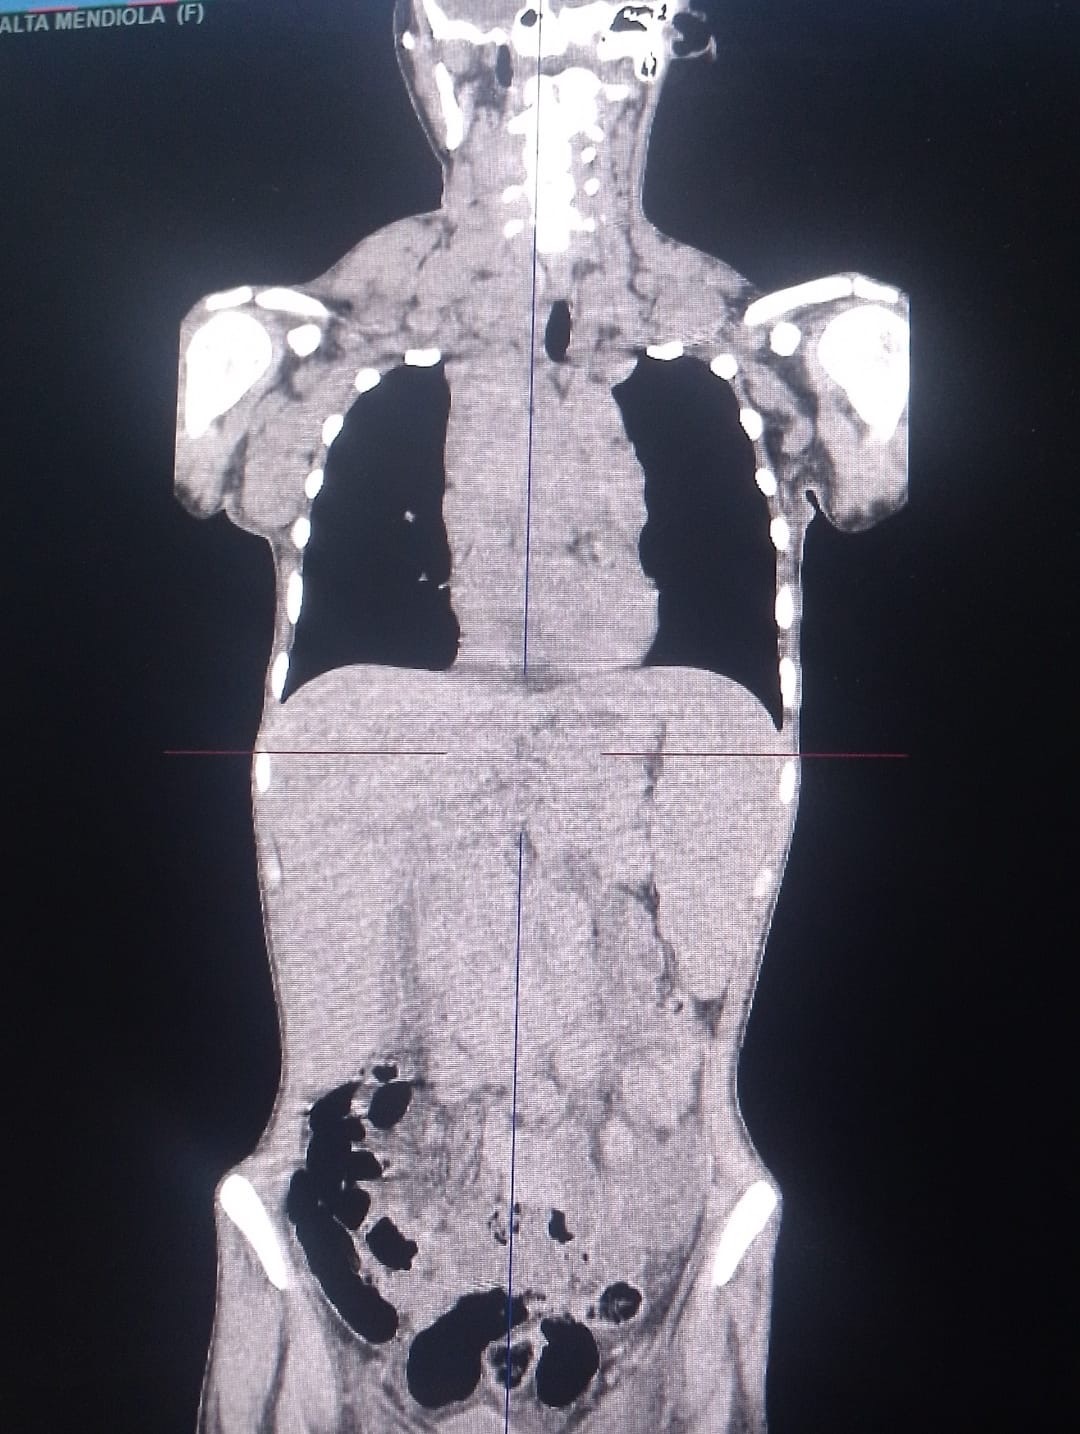

• añadí unas tomografías y ahí se ve como empecé y como salió una de mis últimas tomografías